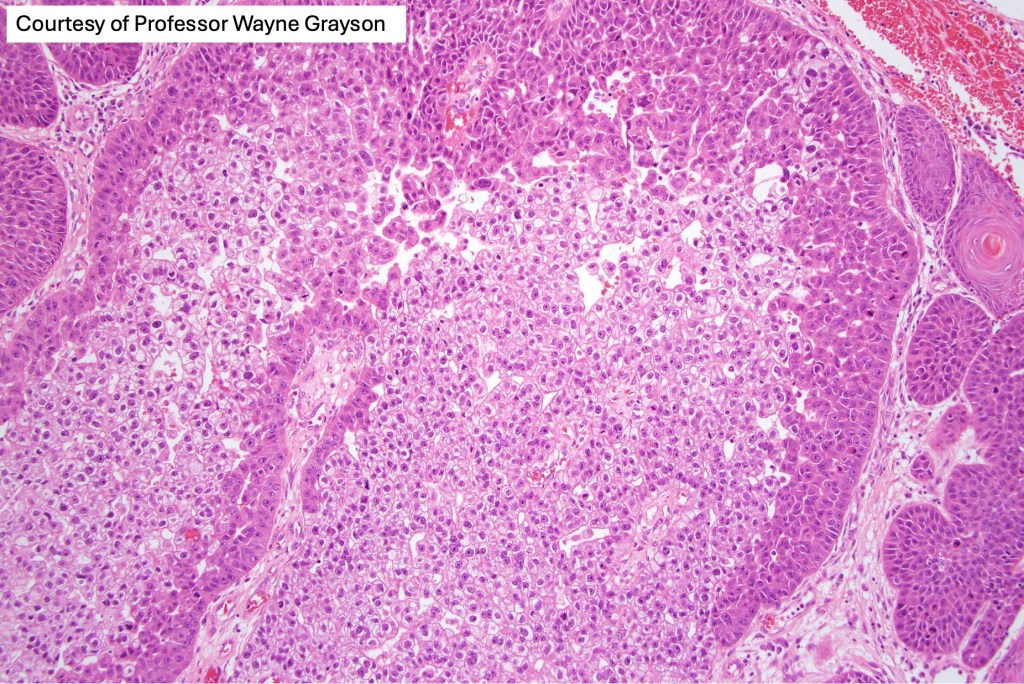

Histological features

•Clear cell change results from cytoplasmic glycogen accumulation

•Can be focal or involve most of the tumor

If obvious squamous differentiation is not apparent, then metastatic clear cell carcinoma is an important differential diagnosis. Clear cell change may also be seen in a wide range of tumors including basal cell carcinoma, trichilemmal carcinoma, clear cell hidradenocarcinoma, porocarcinoma & melanoma. These are all discussed in respective blogs.